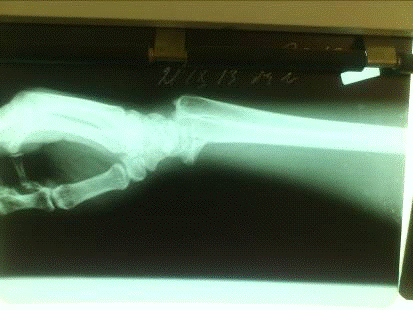

На прицельной рентгенограмме лучезапястного сустава в прямой и боковой проекциях - перелом лучевой кости с тыльным смещением

На рентгенограмме: перелом лучевой кости с тыльным смещением, перелом обеих ветвей правой лобковой кости со смещением отломков

На прицельной рентгенограмме лучезапястного сутава в прямой и боковой проекциях - перелом лучевой кости с тыльным смещением